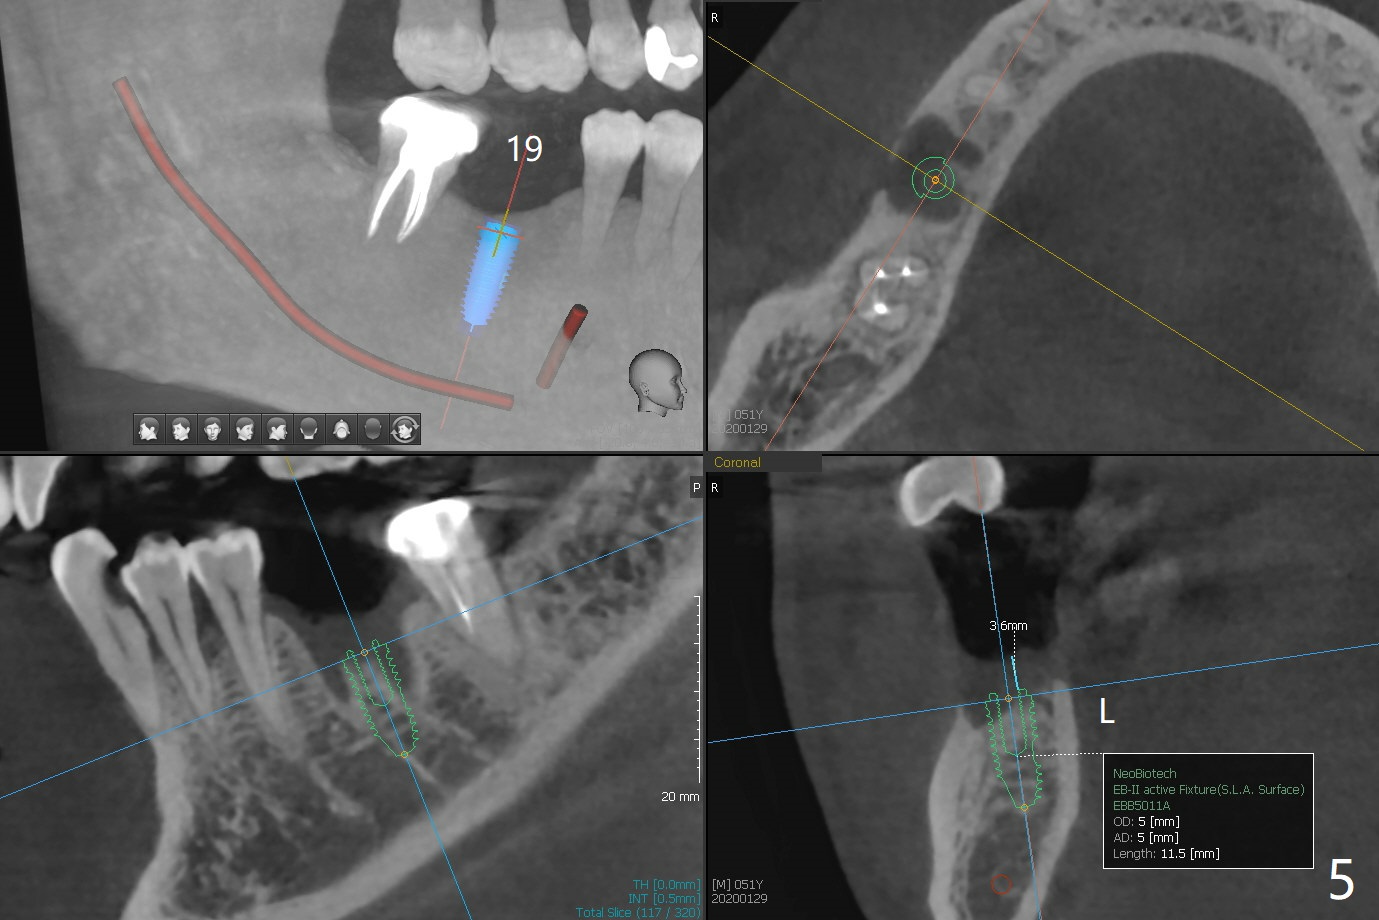

A 51-year-old man with chronic periodontitis requests implants at 19, 24-26 and 30 nearly 2 months post extraction without bone graft (Fig.1). He is willing to quit smoking by using electronic smoke. After SRP, the tooth #6 with supragingival fracture will be saved by post and crown. The mesiodistal space seems to be too narrow for implant (Fig.2). 1-piece implants will be placed at #24 and 26 for FPD (Fig.3,4). Implant placement at #19 and 30 will involve incision, socket redebridement, guide, bone graft (sticky bone), PRF membranes as a barrier and sutures (Fig.5,6).